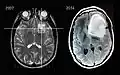

Scanner IRM d'un patient atteint d'un astrocytome montrant l'évolution sur 7 ans.